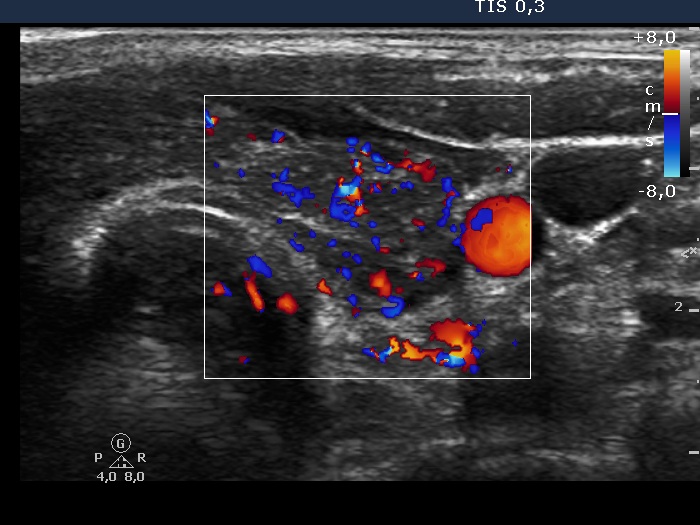

Follow-up examination 15 months after first visit (third row of images):

Ultrasonography: The thyroid was echonormal and contained small hypoechogenic areas. The vascularization was practically absent.